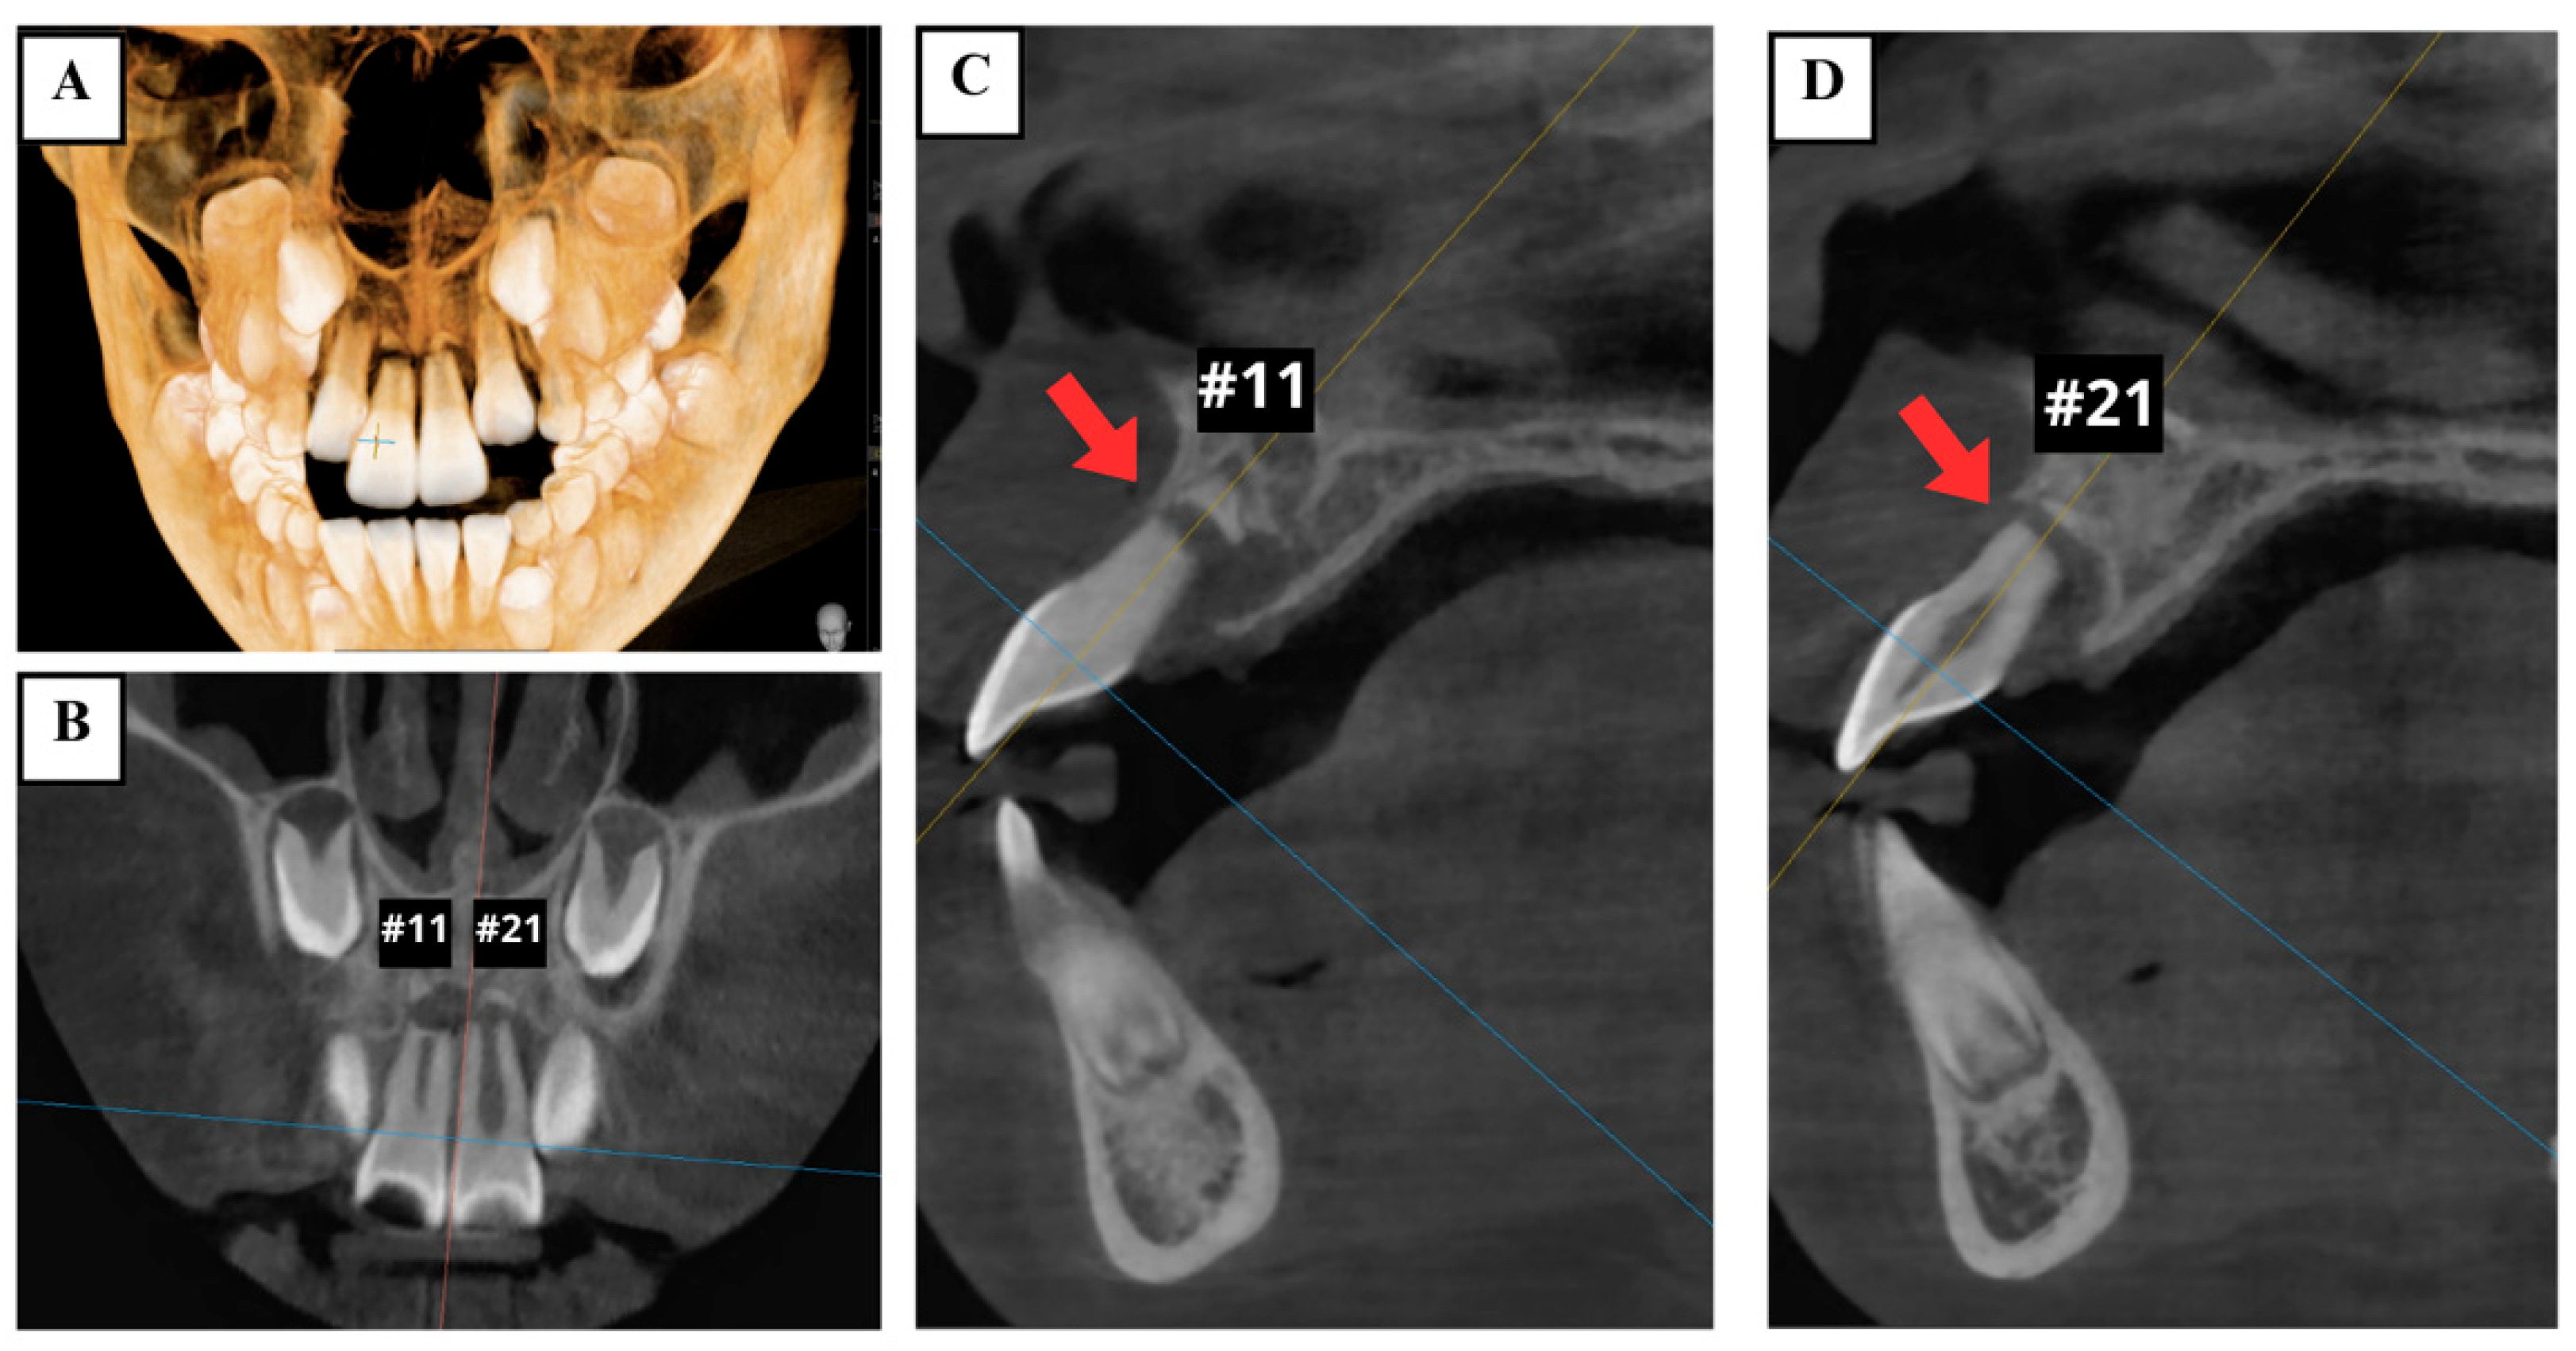

Cone-beam computed tomography (CBCT) demonstrated the presence of horizontal root fractures in the apical third of both maxillary central incisors, leading to separation of the apical and coronal fragments. The traumatized teeth had incomplete root development, wide root canals, and open apices (Figure 3).

Figure 3.

Preoperative CBCT images showing horizontal root fractures in the apical third of two maxillary central incisors (arrows). (A) 3D reconstruction; (B) coronal view; (C) sagittal views of the right maxillary central incisor (tooth #11); and (D) left maxillary central incisor (tooth #21).